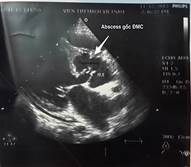

Kết quả siêu âm tim qua thành ngực cho thấy hình ảnh sùi van động mạch chủ, áp xe thành trước động mạch chủ lan tới 1/3 trên vách liên thất gây hở chủ nhiều. Sùi van hai lá gây hở hai lá nhiều và giãn các buồng tim (Hình 1,2). Điện tim đồ cho thấy block nhĩ thất cấp 3 (Hình 3). Cấy máu cấp ở 3 vị trí khác nhau cho kết quả âm tính. Bệnh nhân được hội chẩn nội – ngoại khoa và được chỉ định phẫu thuật cấp cứu.